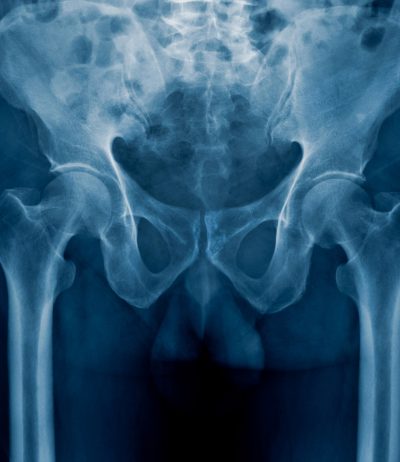

A genitourinary fistula is a connection between any of the reproductive organs with the excretory organs. Normally, these organs all have separate openings. But if a genitourinary fistula, which is a hole or a tear, develops in any of them in the wrong place, the reproductive and excretory organs can become improperly connected.